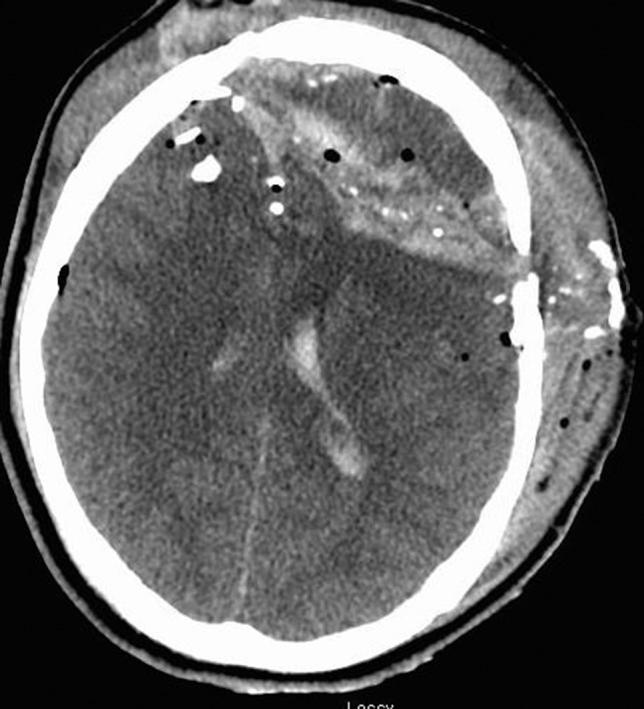

The gunshot wound to the head (GSWH) is associated with a mortality rate of 20-90% in adults and 20-65% in the pediatric population. Due to the high rates of mortality and morbidity, the management of these patients has been a topic of high interest in the neurosurgical community. We present an 18-year-old male suffering a GSWH with the bullet following a transventricular trajectory and crossing the midsagittal plane, creating extensive intracranial injuries. Despite a calculated mortality rate of >97% from these devastating injuries, the patient survived the GSWH and made a remarkable recovery. The young adult brain still maintains a high potential for neurological plasticity. This may partially explain why the young adult population with a severe GSWH can have a better than expected recovery course. Bifrontal GSW injuries may have much better outcomes than more posterior injuries as has been demonstrated in this patient in this case.